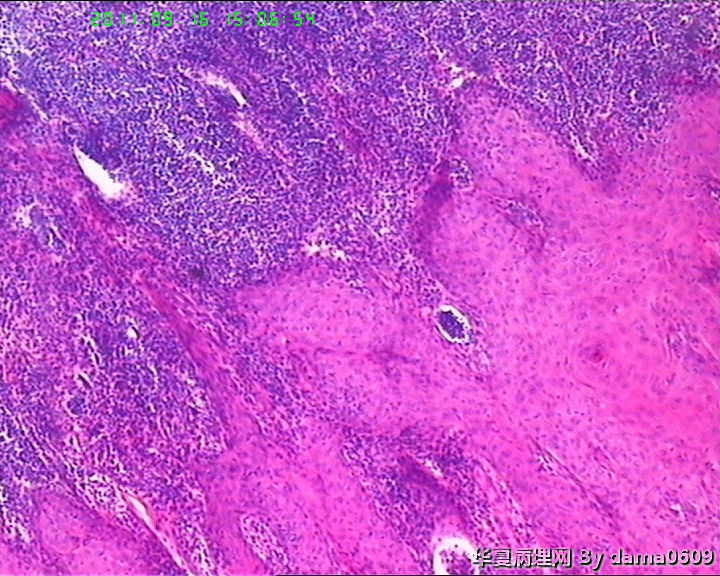

• 背部肿物,急请老师看看!!图4

图4